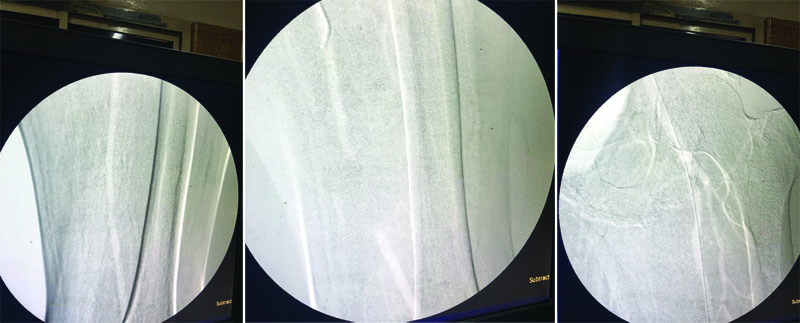

تم اليوم لأول مره إجراء تقنيه توسيع الشرايين للساق باستخدام غاز ثانى أكسيد الكربون (co2) بدلا من استخدام الصبغة...

وقد قام فريق طبى مكون من

أ. د / أيمن حسب الله  -  أ. د / أحمد حسن بكر -  أ. د / هيثم على حسن –  أ. د /  محمود إسماعيل

تحت رعاية الأستاذ الدكتور/ مصطفى سعد - رئيس القسم بإجراء هذه التقنية الحديثة جدا والموجودة في مراكز محدودة جدا على مستوى مصر وتخدم قطاع كبير من المرضى..

وتعتبر هذه التقنيه الحديثة جدا هى الحل الأمثل لمرضى السكر الذين يعانون من انسداد الشرايين مع ارتفاع وظائف الكلى والذى يؤدى استخدام الصبغة فى هذه الحالات إلى الأضرار بالكلى وإجراء الغسيل الكلوي احيانا.. كما يمكن استخدامها فى كل مرضى انسداد الشرايين لحمايتهم من أخطار الصبغة..